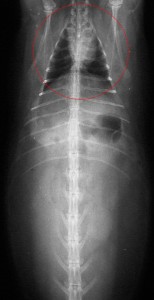

It never hurts to be thorough during this pre-anesthetic exam and take a radiograph (X-ray). The following 3 radiographs, on rabbits that were seemingly normal, show why.

The heart and lungs (within the red circle) are tiny compared to the size of the abdomen. This ratio between lungs and abdomen is much smaller than in other animals, and needs to be closely watched during anesthesia.